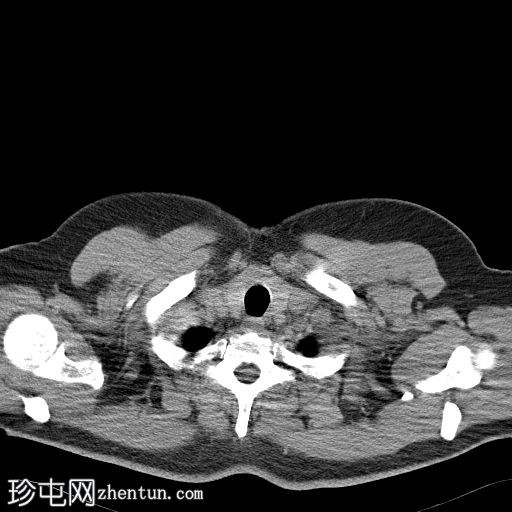

矢状位增强扫描(门静脉期)

3.jpg

盆腔内可见一大小为12 x 17 cm的边界清晰的异质性软组织肿块,向下延伸至下腹部。肿块内未见钙化或脂肪密度影。肿块向下推挤膀胱,并牵拉周围肠袢,但无放射学侵犯证据。未见明显淋巴结肿大、腹水或气腹。未见肺部或骨骼局灶性病变。肝脏可见数个小的单纯性囊肿。患者存在少量Bosniak I型肾囊肿,双侧肾盂肾盏系统饱满。曾行胆囊切除术。